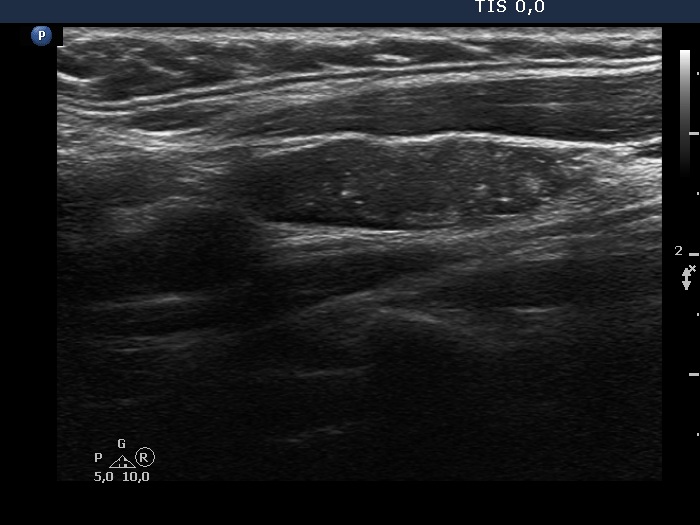

Ultrasonography. The thyroid was echonormal. There were two nodules in the left lobe. The upper lesion was a dominantly isoechoic nodule which had microcalcifications while the lower one was a hypoechoic nodule. There were numerous microcalcification relatively far from the primary tumor focus. The upper nodule was avascular while the lower one presented both intranodular and perinodular blood flow.

A conglomerate of lymph nodes was found 2 cm above the left lobe. The nodes did not have hilum but contained microcalcifications and presented irregular vascular pattern. (This was not noticed on the previous ultrasound examination.)